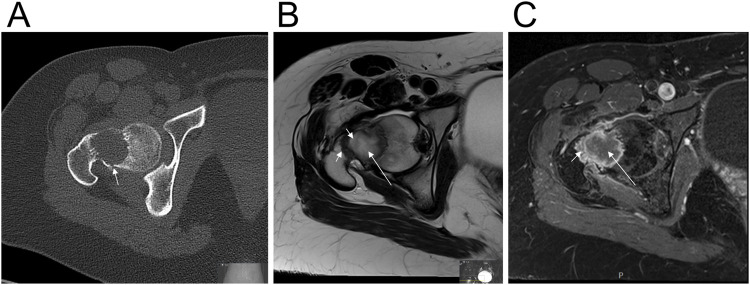

Background: Benign fibro-osseous lesions are characterized by the replacement of normal bone with cellular fibrous connective tissue with new bone formation. The published cytogenetic information on these tumors is limited to only few cases. Here, we report the cytogenetic and molecular genetic findings of a fibro-osseous tumor.

Methods: A fibro-osseous lesion was investigated for genetic abnormalities using banding cytogenetics, fluorescence in situ hybridization (FISH), RNA sequencing, and direct cycle Sanger sequencing.

Results: The karyotype was 46,XX,t(4;11;14;12)(q35;p15;q22;q13)[7]/46,XX [3], with no rearrangement of HMGA2. RNA sequencing revealed two FRMD6::PTH chimeric transcripts, originating from the fusion point 14q22;11p15 of the t(4;11;14;12). In these transcripts, exon 1 of FRMD6 fused to either exon 1 or exon 2 of PTH. Direct cycle sequencing confirmed the presence of these FRMD6::PTH chimeric transcripts.